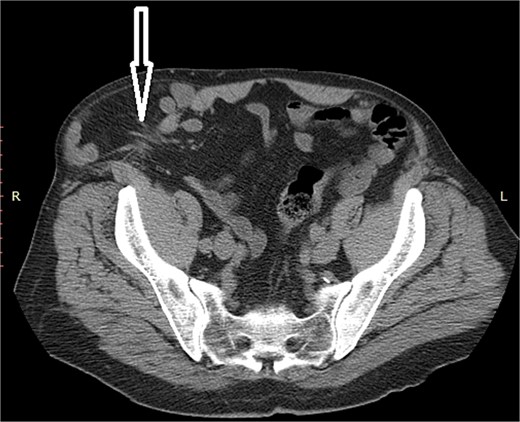

A 72-year-old patient, in good physical condition with a BMI of 26.1, came for an examination due to swelling in the right lateral abdominal wall without swelling of the scrotum. The patient was operated on for a right-sided inguinal hernia as an 8-year-old boy, but there was no appropriate medical documentation for the operative technique used. A month ago, besides the swelling, he experienced occasional abdominal pain and difficulties during physical activities in his garden. During clinical examination, a soft swelling in the right lateral abdominal wall, compressible under palpation was ascertained (Fig. 1). The abdominal ultrasound and contrast abdominal CT showed a thinned right abdominal wall with superficial intestinal loops and the differential diagnosis of a large recurrent inguinal or Spigelian hernia was presumed (Fig. 2). The patient received one dose of prophylactic cephalosporin preoperatively, and was operated on under general endotracheal anesthesia, in a supine position with a lumbar pillow placed for a slight tilt to the left. A right lateral lumbar-inguinal skin incision 4–5 cm above the anterior superior iliac spine in a horizontal direction following the lumbar dermatomal lines was performed. Subcutaneous fat was gently separated and the hernial sac dissection went to its apex below the right costal arch and base to the deep inguinal opening. When the sac was completely freed, the final diagnosis of giant recurrent indirect inguinal hernia (Fig. 3), and the sac with its content was repositioned in the abdominal cavity without opening the abdominal cavity and partial closure of the internal iliac ring was performed with resorptive sutures. After the dissection of the inguinal ligament up to the pubic tubercle (without extending the skin incision) a 15 × 12 cm polypropylene mesh was placed (Fig. 4), fixed to the pubic tuberculum and conjoint tendon with a laparoscopic taker (Fig. 5), and the ileopubic ligament partly with individual and partly with continuous non-absorbable polypropylene 2/0 suture. An opening for the spermatic cord was provided and medially the mesh was fixed with individual resorptive stitches (Fig. 6). The aponeurosis of the external oblique muscle was closed as much as it allowed to be approximated followed by individual subcutaneous and skin stitches (Fig. 7). The operating time was 65 minutes without blood loss and the patient had a quick and satisfactory recovery. He was discharged from the hospital on the third post-op day, and the skin stitches were removed on the 14th day. One month after the surgical treatment the patient was in good condition without any complaints (Fig. 8).

Non-contrast abdominal CT, an arrow pointing to the abdominal wall defect and intestine protrusion